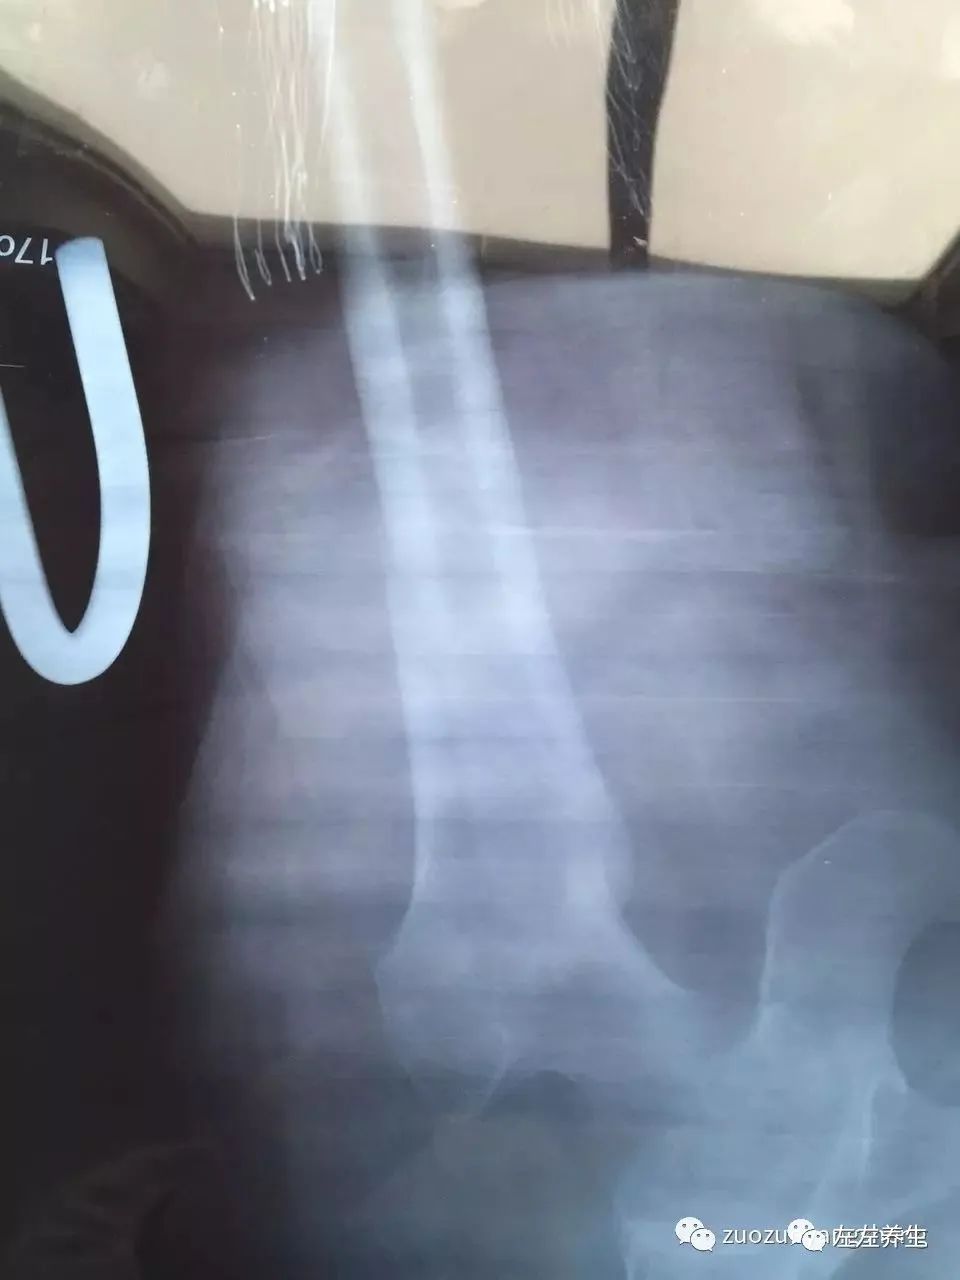

3、 牵引6周后

②4牵引6周后(点击可看大图)

牵引期间,在骨折处时敷药酒时敷姜膏、贴暖宝宝、喝姜汤,后改为喝参粉汤(1天4次)。医生说牵引需要8到12周,但我母亲在牵引4周时就已长出一些骨架,考虑到年龄因素继续牵引至6周,拍片显示骨头愈合非常良好,开始慢慢撤牵引,医生建议再继续在医院多观察两周,然后就可以回家安养。在这治疗过程当中,运用原始点的方法帮着内外调理,取得了显著的效果,被医生称之为奇迹,并成为医院的案例,可以作为以后同样患者治疗的一个指导。

附:2017年3月27日最新的片子